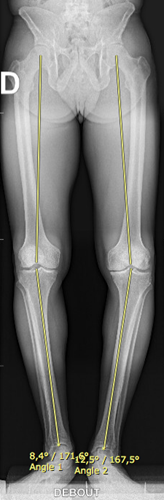

Le bilan comprend des radiographies standards en charge, une goniométrie pour mesurer l’axe mécanique.

Eventuellement un arthroscanner ou IRM afin de cartographier votre arthrose.

Avec ces examens, on peut ainsi prévoir un traitement sur mesure de l’arthrose.